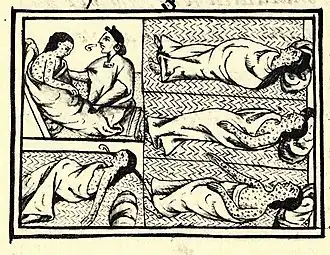

Medicine has been practiced since prehistoric times, and for most of this time it was an art (an area of creativity and skill), frequently having connections to the religious and philosophical beliefs of local culture. For example, a medicine man would apply herbs and say prayers for healing, or an ancient philosopher and physician would apply bloodletting according to the theories of humorism. In recent centuries, since the advent of modern science, most medicine has become a combination of art and science (both basic and applied, under the umbrella of medical science). For example, while stitching technique for sutures is an art learned through practice, knowledge of what happens at the cellular and molecular level in the tissues being stitched arises through science.

Prescientific forms of medicine, now known as traditional medicine or folk medicine, remain commonly used in the absence of scientific medicine and are thus called alternative medicine. Alternative treatments outside of scientific medicine with ethical, safety and efficacy concerns are termed quackery. (Full article...)